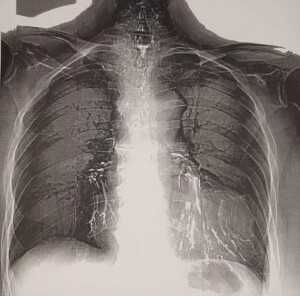

Рисунок 2. Остатки бария сульфата в бронхах у пациентки с пищеводно-бронхиальными свищами